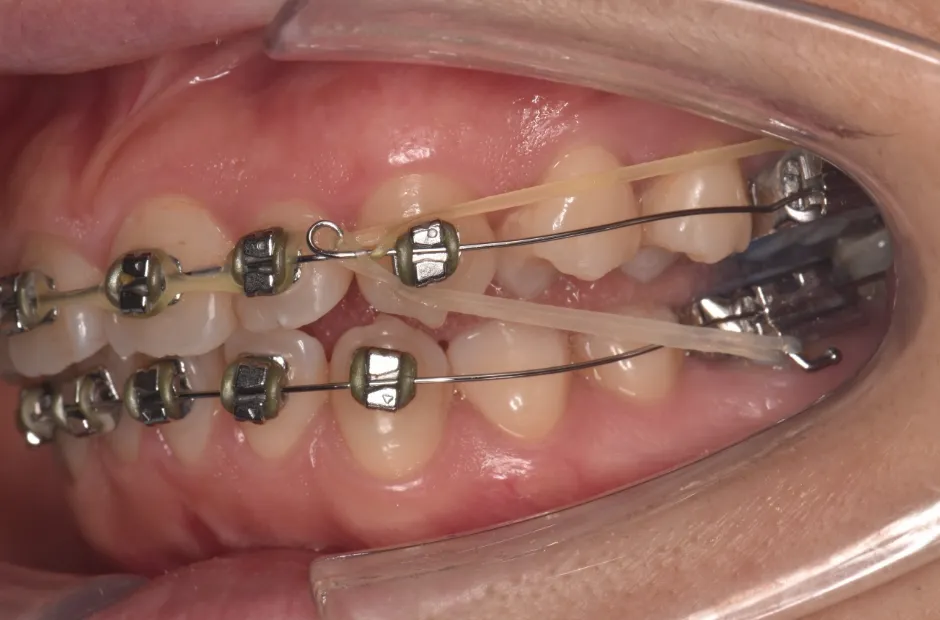

| 診断名・主訴 | 開咬 |

|---|---|

| 年齢・性別 | 23歳・女性 |

| 治療期間・回数 | 1年 12回 |

| 治療に用いた主な装置 | クワドヘリックス(QH)+タングガード → ロール付きリンガルアーチ |

| 抜歯部位 | 左右下8番 |

| 治療費 | 70万円(税抜) |

| リスク・副作用 | 装置による違和感・疼痛・歯肉退縮・歯根吸収・虫歯のリスクなど |

治療前

治療後